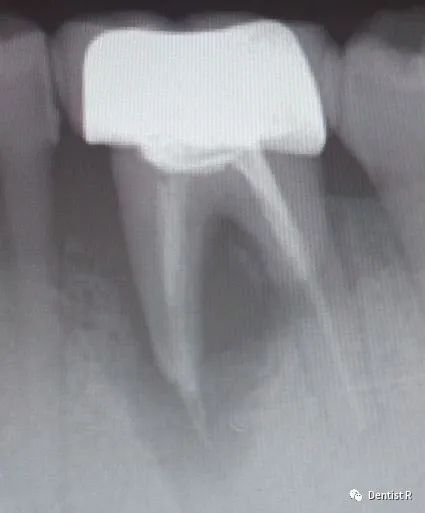

牙根有问题就更要拍片了

牙根是埋在牙槽骨中的

医生如果想了解

牙根的形态、走向、长度

根尖周有无病变及病变范围,

或者怀疑其他无法确认的问题,

必须通过X光片或者CT才能确诊,

制定合适的治疗计划。